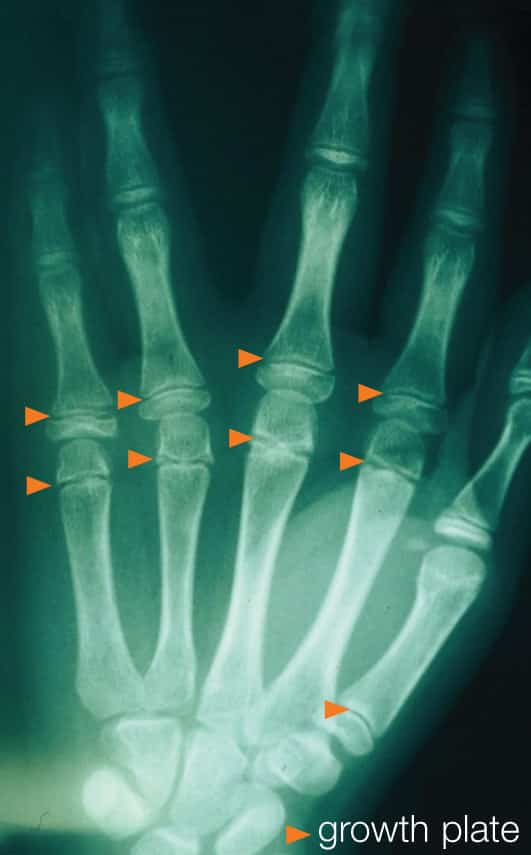

Children’s bones also have growth plates, which are bands of softer cartilage near the end of the bone that allow the bone to elongate as it grows. Since the cartilage does not have calcium, it appears as a clear band on an X-ray (see Figure 1b). Since the bone is softer in the area of the growth plate, it is common to see fractures in this zone. Although injury to the growth plate could affect that bone’s growth, many of these fractures in the hand and wrist heal well without later deformity.